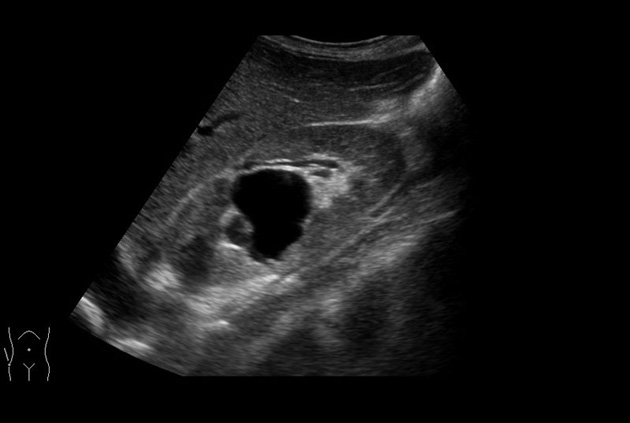

Trapezoidal Scan

Use of trapezoid mode with the linear transducer extends the width of the field of view permitting a greater understanding of the orientation and size of the target and its surroundings.